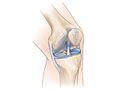

Magnetic Resonance Imaging (MRI) of the KneeSkip to the navigationTest OverviewMagnetic resonance imaging (MRI) is a test

done with a large machine that uses a magnetic field and pulses of radio wave

energy to make pictures of the knee. Muscles,

ligaments,

cartilage, and other joint structures are often best

seen with an MRI. In many cases MRI gives information about structures in the